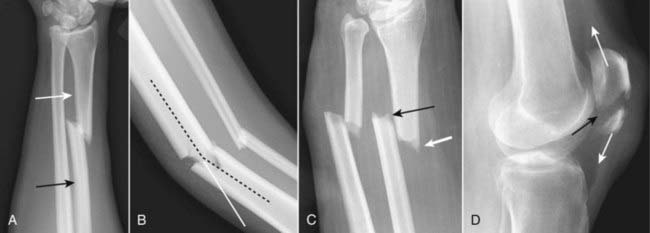

Figure 22-27 Fracture of radial head with joint effusion, frontal (A) and lateral (B) views.

Radial head fractures (dotted black arrows) are the most common fractures of the elbow in an adult. Look for fat appearing as a crescentic lucency along the dorsal aspect of the distal humerus (solid black arrow) caused by intracapsular, extrasynovial fat that is lifted away from the bone by swelling of the joint capsule due to a traumatic hemarthrosis—the positive posterior fat-pad sign. Virtually all studies of bones will include at least two views at 90° angles to each other called orthogonal views. Many protocols call for two additional oblique views which enable you to visualize more of the cortex in profile.

Figure 22-28 Supracondylar fracture.

A supracondylar fracture of the distal humerus is a common fracture in children, and its findings may be subtle. Most of these fractures produce posterior displacement of the capitellum of the distal humerus. On a true lateral film, the anterior humeral line (a line drawn tangential to the anterior humeral cortex and shown here in black) should bisect the middle portion of the capitellum (solid white arrow). When there is a supracondylar fracture, this line will pass more anteriorly, as it does here. There is a positive posterior fat pad sign present (solid black arrow).